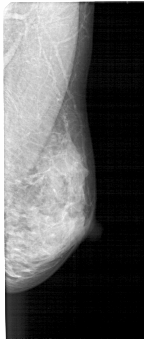

A_1446_1.LEFT_MLO

LEFT_MLO LINES 5341 PIXELS_PER_LINE 2461 BITS_PER_PIXEL 12 RESOLUTION 43.5 OVERLAY